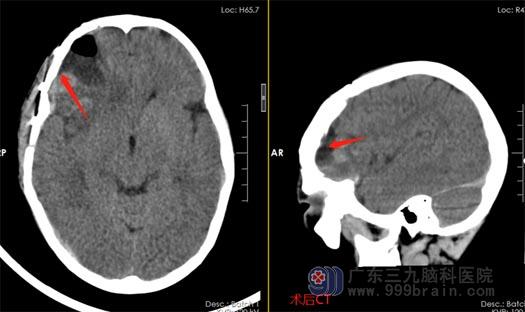

在亲戚的帮助下,林林父亲联系到了广东三九脑科医院鲁明副院长,在鲁院长的安排下,孩子连夜转到了广东三九脑科医院。神经外五科王国良主任带领的神经外科团队对林林的病情进行讨论后,急诊行右额叶血肿清除+右侧额颞部凹陷性骨折整复术,直到凌晨手术才结束。医生很有信心的对家属说:手术很成功,你们可以放心了。

▲术后

术后第一天,林林恢复很好,已经完全清醒,手脚活动也恢复正常,爸妈激动不已,原以为孩子伤势这么严重,很难被救回来,差点就失去希望。